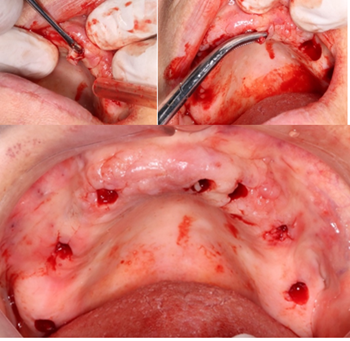

Step 6: Removal of Nasopalatine Duct Cyst

Nasopalatine duct cyst (NPDC) is a non-odontogenic, developing epithelial cyst that represents 1% of all maxillary cysts. It is commonly caused by the spontaneous growth of epithelial tissue remains; however, trauma, bacterial infection, and mucus retention can also cause proliferation. Due to its slow growth and asymptomatic character, the cyst is frequently discovered by accident during routine clinical and radiographic tests [7].

Recurrence is rare, occurring in 0-11% of cases, according to reports. Following surgery, full reconstruction of the bones within the bony defect is expected (8). The intra-oral assessment showed diffuse non-tender isolated swelling in the anterior mid-palatal region (Figure 13). Radiographically, it presents as a well-defined oval or round radiolucency in the maxillary anterior tooth region (Figure 14).

The treatment is done by complete enucleation of the cyst via palatal approach under local anesthesia. Palatal incision was performed and detachment of palatal mucosa in the region between the right and left canines approximately. Dissection was performed between the cystic capsule and the adherent mucosa, followed by cyst enucleation and cleaning of the cavity. The flap was sutured with 3/0 silk.

Figure 13: Occlusal view of the maxilla.

Figure 14: Paraxial cut of the cyst.

Figure 15: Incision and removal of the cyst.

Figure 16: Size of the cyst.